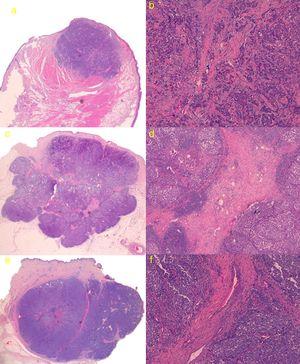

El estudio histológico de la tumoración completa se pudo llevar a cabo en 3 de los pacientes, debido a que 2 de las lesiones (casos 2 y 5) regresaron de forma espontánea tras la biopsia cutánea (confirmándose mediante estudio histológico de pieza quirúrgica). En los 3 casos la tumoración presentó un patrón sólido de crecimiento, uno de los casos con bordes espiculados y los otros 2 tumores con bordes mejor delimitados y estructura lobulada. Los 3 tumores presentaban trabéculas fibrosas separando las células, el primer caso presentó tractos finos con escasas estructuras vasculares, mientras que los 2 tumores restantes presentaron tractos fibrosos gruesos con numerosas estructuras vasculares en su interior (fig. 3). Se realizó inmunohistoquímica en los 5 casos resultando positivas para cromogranina, sinaptofisina, CD56 y paranuclear con citoqueratina 20, siendo negativas para CD45, proteína S100 y TTF-1.

a) Caso 1: lesión con patrón sólido de crecimiento con bordes ligeramente espiculados. Hematoxilina-eosina (H&E); b) Detalle de trabéculas fibrosas en forma de tractos finos con escasas estructuras vasculares (H&E ×100); c) Caso 3: tumoración con bordes mejor delimitados y estructura lobulada, con tractos fibrosos que se parece corresponder con las líneas intralesionales hiperecogénicas que se visualizan en la ecografía cutánea en modo B (H&E); d) Detalle de tractos fibrosos gruesos con numerosas estructuras vasculares en su interior (H&E ×40); e) Caso 4: lesión lobulada con tracto fibroso grueso perpendicular a la epidermis, que parece corresponderse ecográficamente con línea hipoecoica visualizada en modo B; f) Detalle de tracto fibroso grueso central con estructuras vasculares de mayor calibre que en el caso 3 (H&E ×100).